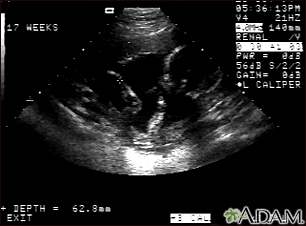

Ultrasound, normal fetus - arm and legsBackUltrasound, normal fetus - arm and legsThis is a normal fetal ultrasound performed at 17 weeks gestation. This is the type of image pregnant mothers may see on the ultrasound screen, or that the technician may print. It shows the head on the right, and the cross hair pointing to the left ankle. The left leg and arm are visible in the center of the screen. E-mail FormEmail ResultsName:Email address:Recipients Name:Recipients address:Message: